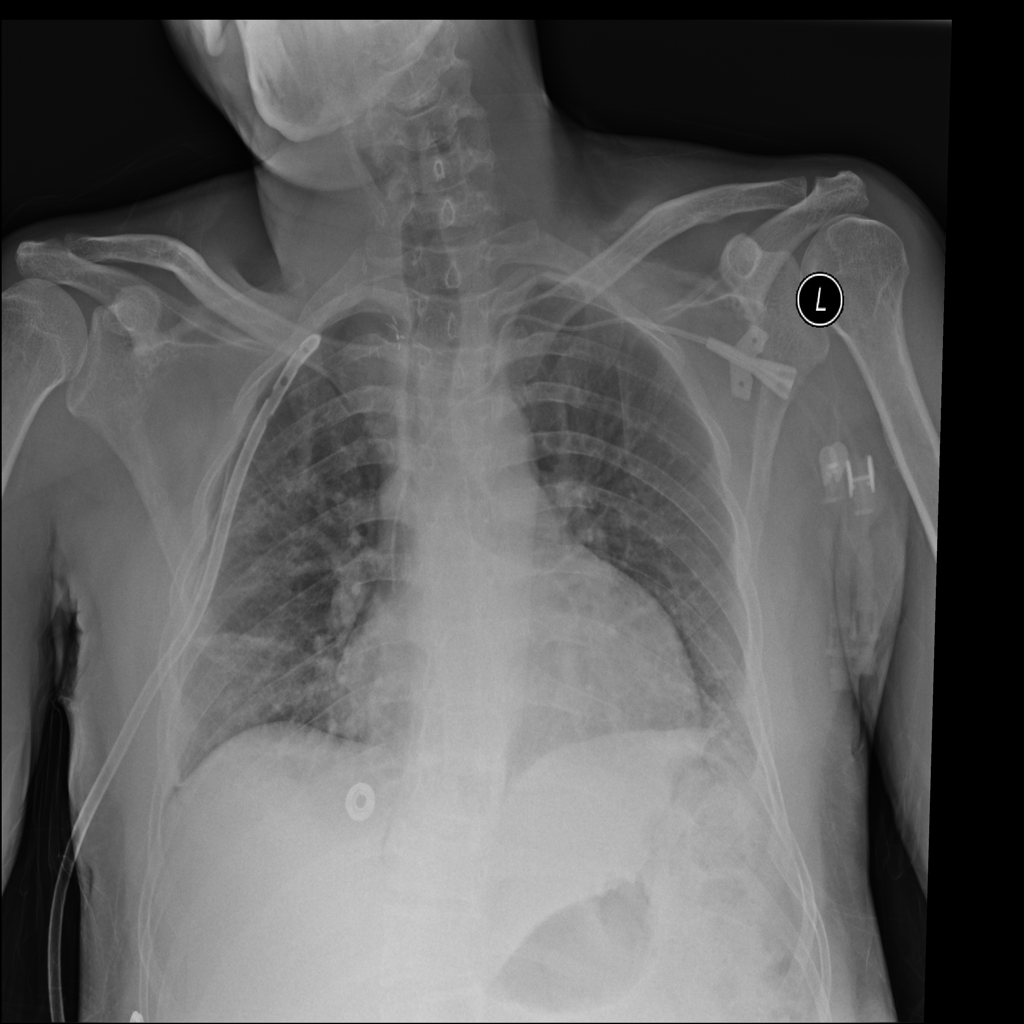

PAT-BA68 · IMG-003Atelectasis

PAT-BA68 · IMG-003

AP